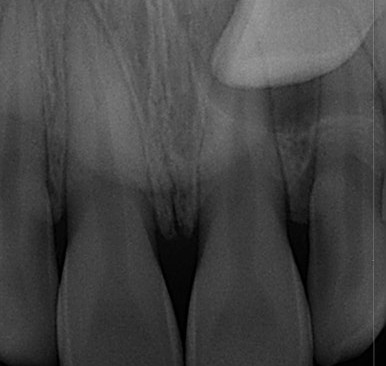

부산매복치아교정 키다리아저씨치과에 처음 내원하셨을 때의 X-ray 사진입니다.

좌측 사진은 파노라마라고 하는 전체가 다 나오는 사진이고, 우측 사진은 해당 부위만 확대해서 찍은 사진입니다.

화살표 표시가 바로 송곳니가 매복이 되어있는 모습입니다. 수직하게 내려오지 못하고 무시무시하게 가로로 누워있는 모습입니다. 입 안에서도 전혀 관찰되지 않고 오로지 뼈속에 있는 상태입니다.

이럴 경우 평면적인 2D X-ray로 정확한 판단이 되지 않습니다.

3차원 CT를 통해 더 정확한 위치를 파악할 필요가 있습니다.